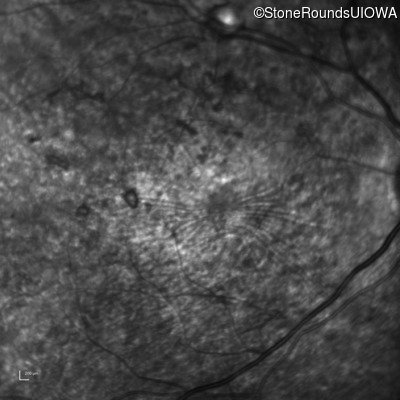

Infrared Fundus Photograph - Left - 10/700 sc

Exemplar